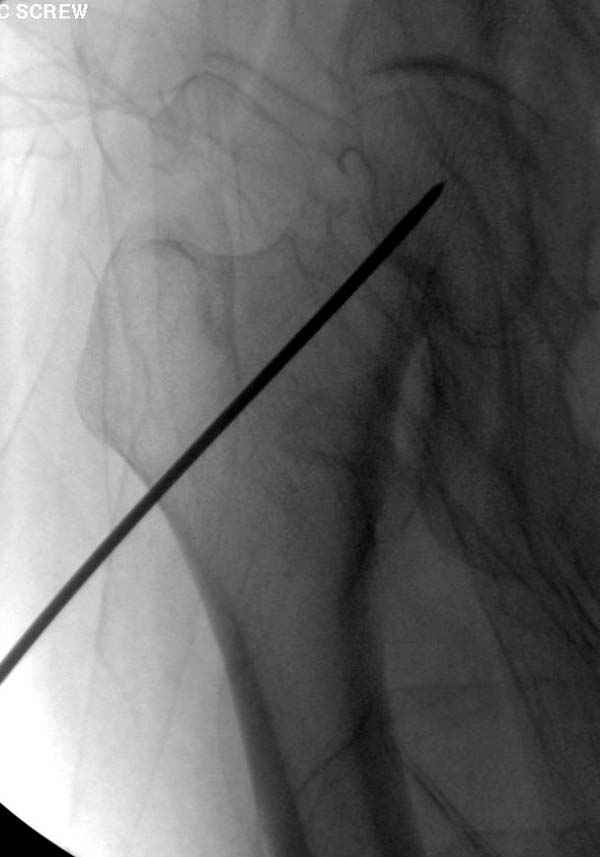

в течение первых 72 часов после перелома, остеосинтез тремя спонгиозными шурупами.

Профилактику дальнейшего раскола неполного перелома шейки провели тремя канюлированными шурупами.

Наверное речь идет насчет parallel guide из набора. Применяем по возможности всегда, но,

как видно на снимке, не всегда получается

паралельно.

Такие несмещенные переломы обычно для молодых резидентов, и бывают технические неточности, но в этом случае посчитали фиксацию адекватной.